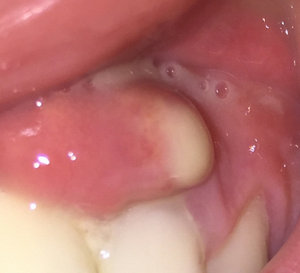

Два года назад мне выдрали зуб, было все хорошо два года. Запломбировали зуб поставили штифт, после возникла какая-то шишка. Пошла к хирургу, сказали киста, вырезали дней шесть назад, шишка стала еще больше, когда трогаешь чувствуешь, что она там есть, сегодня сходила к хирургу, сказала эту шишку постоянно массировать, и антибиотики прописали. Как говорит хирург, там опять образовалась пустота в этом же месте и по какой-то причине она не зарастает. Если она не пройдет, сказали пошлют на биопсию.

Мможет ли, что вот этот зуб со штифтом дает такую реакцию? Температура 37 - 37.3, у хирурга дошло уже дело до биопсии. Подскажите, может, и не надо эту шишку трогать, это же воспалительный процесс какой-то?

Возможно имеется припухлость, и это неотъемлемая часть обострения. Да, имеется костный дефект и зуб, который требует лечения ввиду неграмотного эндодонтического лечения, повлекшего за собой периодонтит. Я вам уже писал, об этом. На мой взгляд, ваш доктор немного лукавит, и биопсия тут вообще не нужна. Даже немного смешно читать такие рекомендации врачей. Сделайте К/Т (трехмерный снимок) и обратитесь к грамотному врачу.